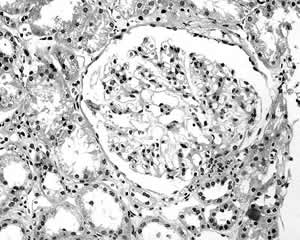

肾穿病理结果 光镜:全片共32个肾小球,6个球性硬化,余肾小球细胞数未见明显增多,球囊腔普遍增宽,大部分肾小球体积增大,可见节段性系膜细胞增生和系膜基质增多。毛细血管开放良好,肾小球基底膜(GBM)未见明显增厚,部分肾小球旁器肥大(图1,图2),可见入球小动脉壁增厚及玻璃样变。部分肾小管上皮细胞可见浊肿及气球样变性,可见小灶性肾小管基底膜(TBM)增厚及小管萎缩,肾间质内小叶间动脉壁增厚及玻璃样变。免疫荧光:全部阴性。

图1 肾小球体积增大,球囊腔增宽,肾小球旁器肥大(HE,×400)